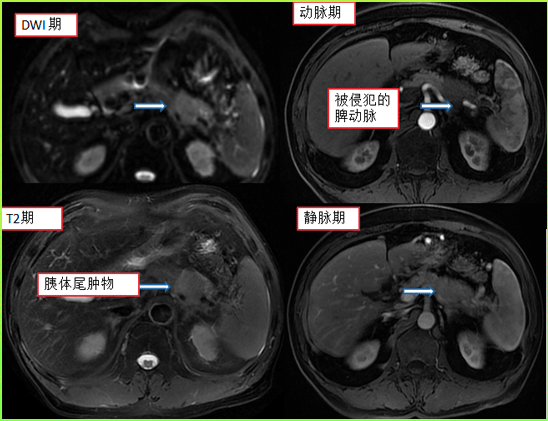

前一段时间就碰到一个七十来岁的老大爷,在当地医院体检时发现胰腺体尾部上长了个肿物,复查增强核磁、PET-CT等检查都提示恶性可能性大。

患者术前的核磁影像